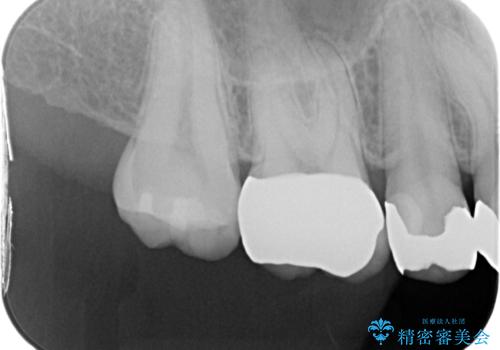

- 銀歯のセラミックへのやり替えをご希望で来院されました。

銀歯が入ってる歯は複数箇所ありましたが、咬合力がより強く破折リスクが高い奥歯から治療を開始してます。

奥歯の噛み合わせが強く、治療後にセラミックが割れるリスクがあった為マウスピースの装着をして頂いてます。

他の銀歯については患者様のご希望のタイミングで治療していく予定です。